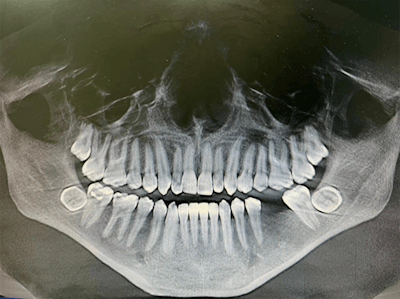

In the case report, the authors described how during the man's routine dental visit, bilateral impacted mandibular third molars were identified on a panoramic dental x-ray. The molars were transverse in the linguobuccal direction. A cone-beam computed tomography (CBCT) scan confirmed the molars were positioned in a linguobuccal direction on both sides, with thinning on the lingual cortical plates. No pathological findings were associated with the molars, the authors wrote.